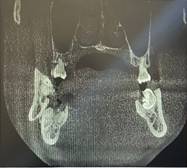

Se decidió realizar un bloqueo mandibular con barras de Erich y posteriormente ingresar al centro quirúrgico; bajo anestesia general se aplica una infiltración de anestésico local (lidocaína 2 % con epinefrina 1:80:000 ppm) en el sitio de la fractura con el objetivo de facilitar la hemostasia.

Mediante el electro bisturí en corte y coagulación de 40 watts se realizó una incisión vestíbulo mandibular con el fin de visualizar la fractura, posterior a ello se redujeron los fragmentos óseos y se estabilizo con una placa de sistema 2.0 (sistema de fijación rígido para buco - maxilofacial) sujetada a 4 tornillos, finalizada la colocación de la placa se sutura utilizando vicryl 3/0, al ser un material reabsorbible, no hubo necesidad de cortar puntos. (Figura 2)

Figura 2. A, B y C. Procedimiento quirúrgico.